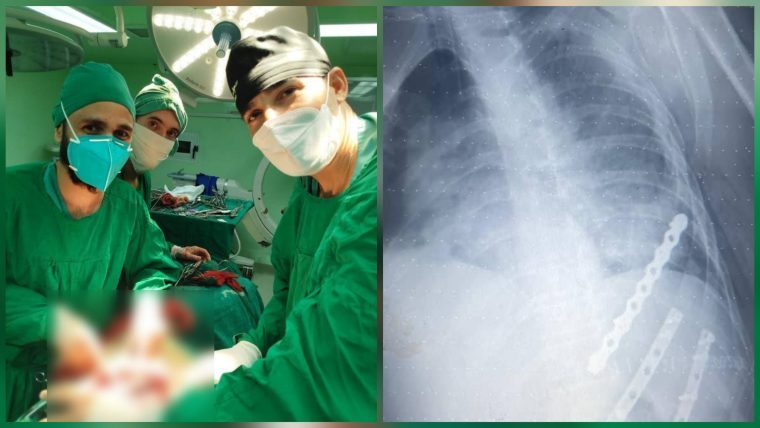

El paciente en estado más crítico fue identificado como Ernel Sánchez González, quien presentó un trauma torácico grave, diagnosticado como tórax batiente. Debido a la complejidad de la lesión, el equipo médico decidió realizar una cirugía inmediata.

El hospital destacó que Sánchez González fue el único de los heridos que necesitó intervención quirúrgica. El procedimiento fue liderado por el Dr. Rubén Alejandro Suárez Ricardo, especialista de segundo grado en Medicina General Integral y de primer grado en Cirugía, junto a los doctores José Infante Valdés (residente de cuarto año), Miguel Agüero Rodríguez y David Granjel Mano (residentes de segundo año), además del equipo de anestesia y enfermería.

Gracias a la rápida actuación y coordinación del personal médico, la operación concluyó con éxito. El paciente se encuentra estable y fuera de peligro, bajo observación en la sala de cuidados posoperatorios.